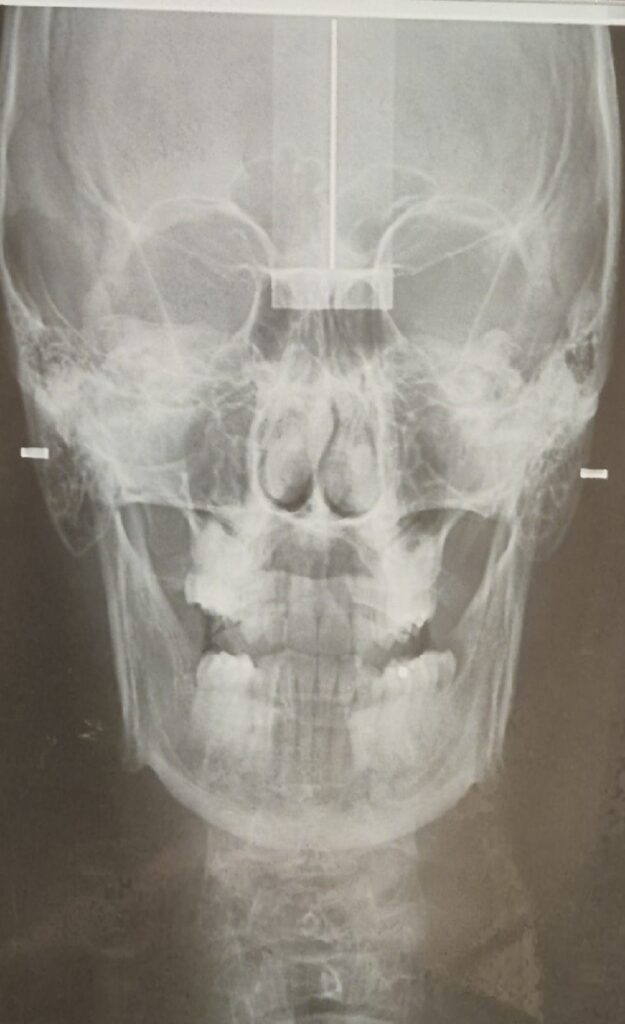

Questa ragazza invece ha un grado di Dis-Equilibrio più evidente e l’evidenza del confronto prima e dopo è palese:

A livello di rx possiamo dire che cranio e mandibola, prima e dopo, sono diventati simmetrici applicando la scoperta del Meccanismo OG. Un evento esclusivo mai visto in tutto il mondo accademico e non, in tutto il pianeta.

I condili della mandibola si riallineano, si riallineano le ossa SUI TRE PIANI SPAZIALI ruotando tra loro e inclinandosi fino ad arrivare ad una posizione di simmetria e di EQUILIBRIO MECCANICO ABITUALE.

Per la rx a destra abbiamo ricevuto complimenti anche da una prestigiosa università italiana che è tra le più prestigiose del mondo.

Un esempio di denti bellissimi senza malocclusione ma su un rapporto scheletrico in Dis-Equilibrio:

Un esempio di rapporto scheletrico in Equilibrio con malocclusione:

Secondo voi quale dei due individui delle rx ha una condizione di vita migliore?

Quello con la malocclusione.

E’ in Equilibrio Meccanico Abituale.

Avrà tutta la forza e l’animo per farsi fare i denti belli.